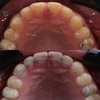

Diş Çapraşıklığı